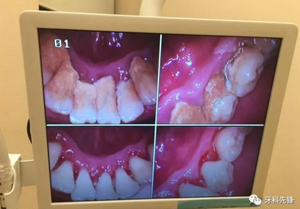

一口老牙,全靠結(jié)石在撐著?

臨床上確實存在這樣的情況,但是作口腔醫(yī)生,我為一名可以負責(zé)任的告訴大家,如果不清除掉牙結(jié)石后果會更加嚴重,甚至有脫落的風(fēng)險。原理是什么呢?因為牙結(jié)石、牙菌斑的破壞能力是極其強大的,只要它存在就會一直不斷的刺激壓迫牙齦,時間久了則會導(dǎo)致牙齦紅腫出血、牙槽骨吸收、牙齦萎縮、牙齒松動甚至脫落等情況,這是一個緩慢發(fā)展的病變過程,單純的靠牙結(jié)石撐住牙齒不讓其出現(xiàn)病理性移動從根本上講是極其不現(xiàn)實的,有點兒“掩耳盜鈴”的意味,不僅撐不住反而會加快牙齒松動、脫落。很可怕吧,尤其是對于我們成年人來說,現(xiàn)有且僅有的一副恒牙竟然還被牙結(jié)石牙菌斑禍害成這個樣子,應(yīng)該算是一種不幸吧!